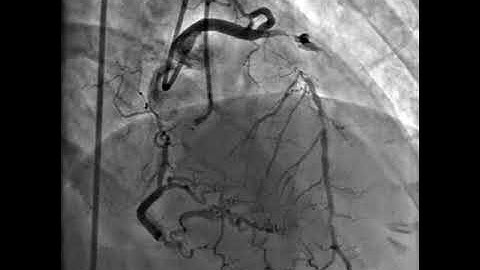

ostial LAD CTO